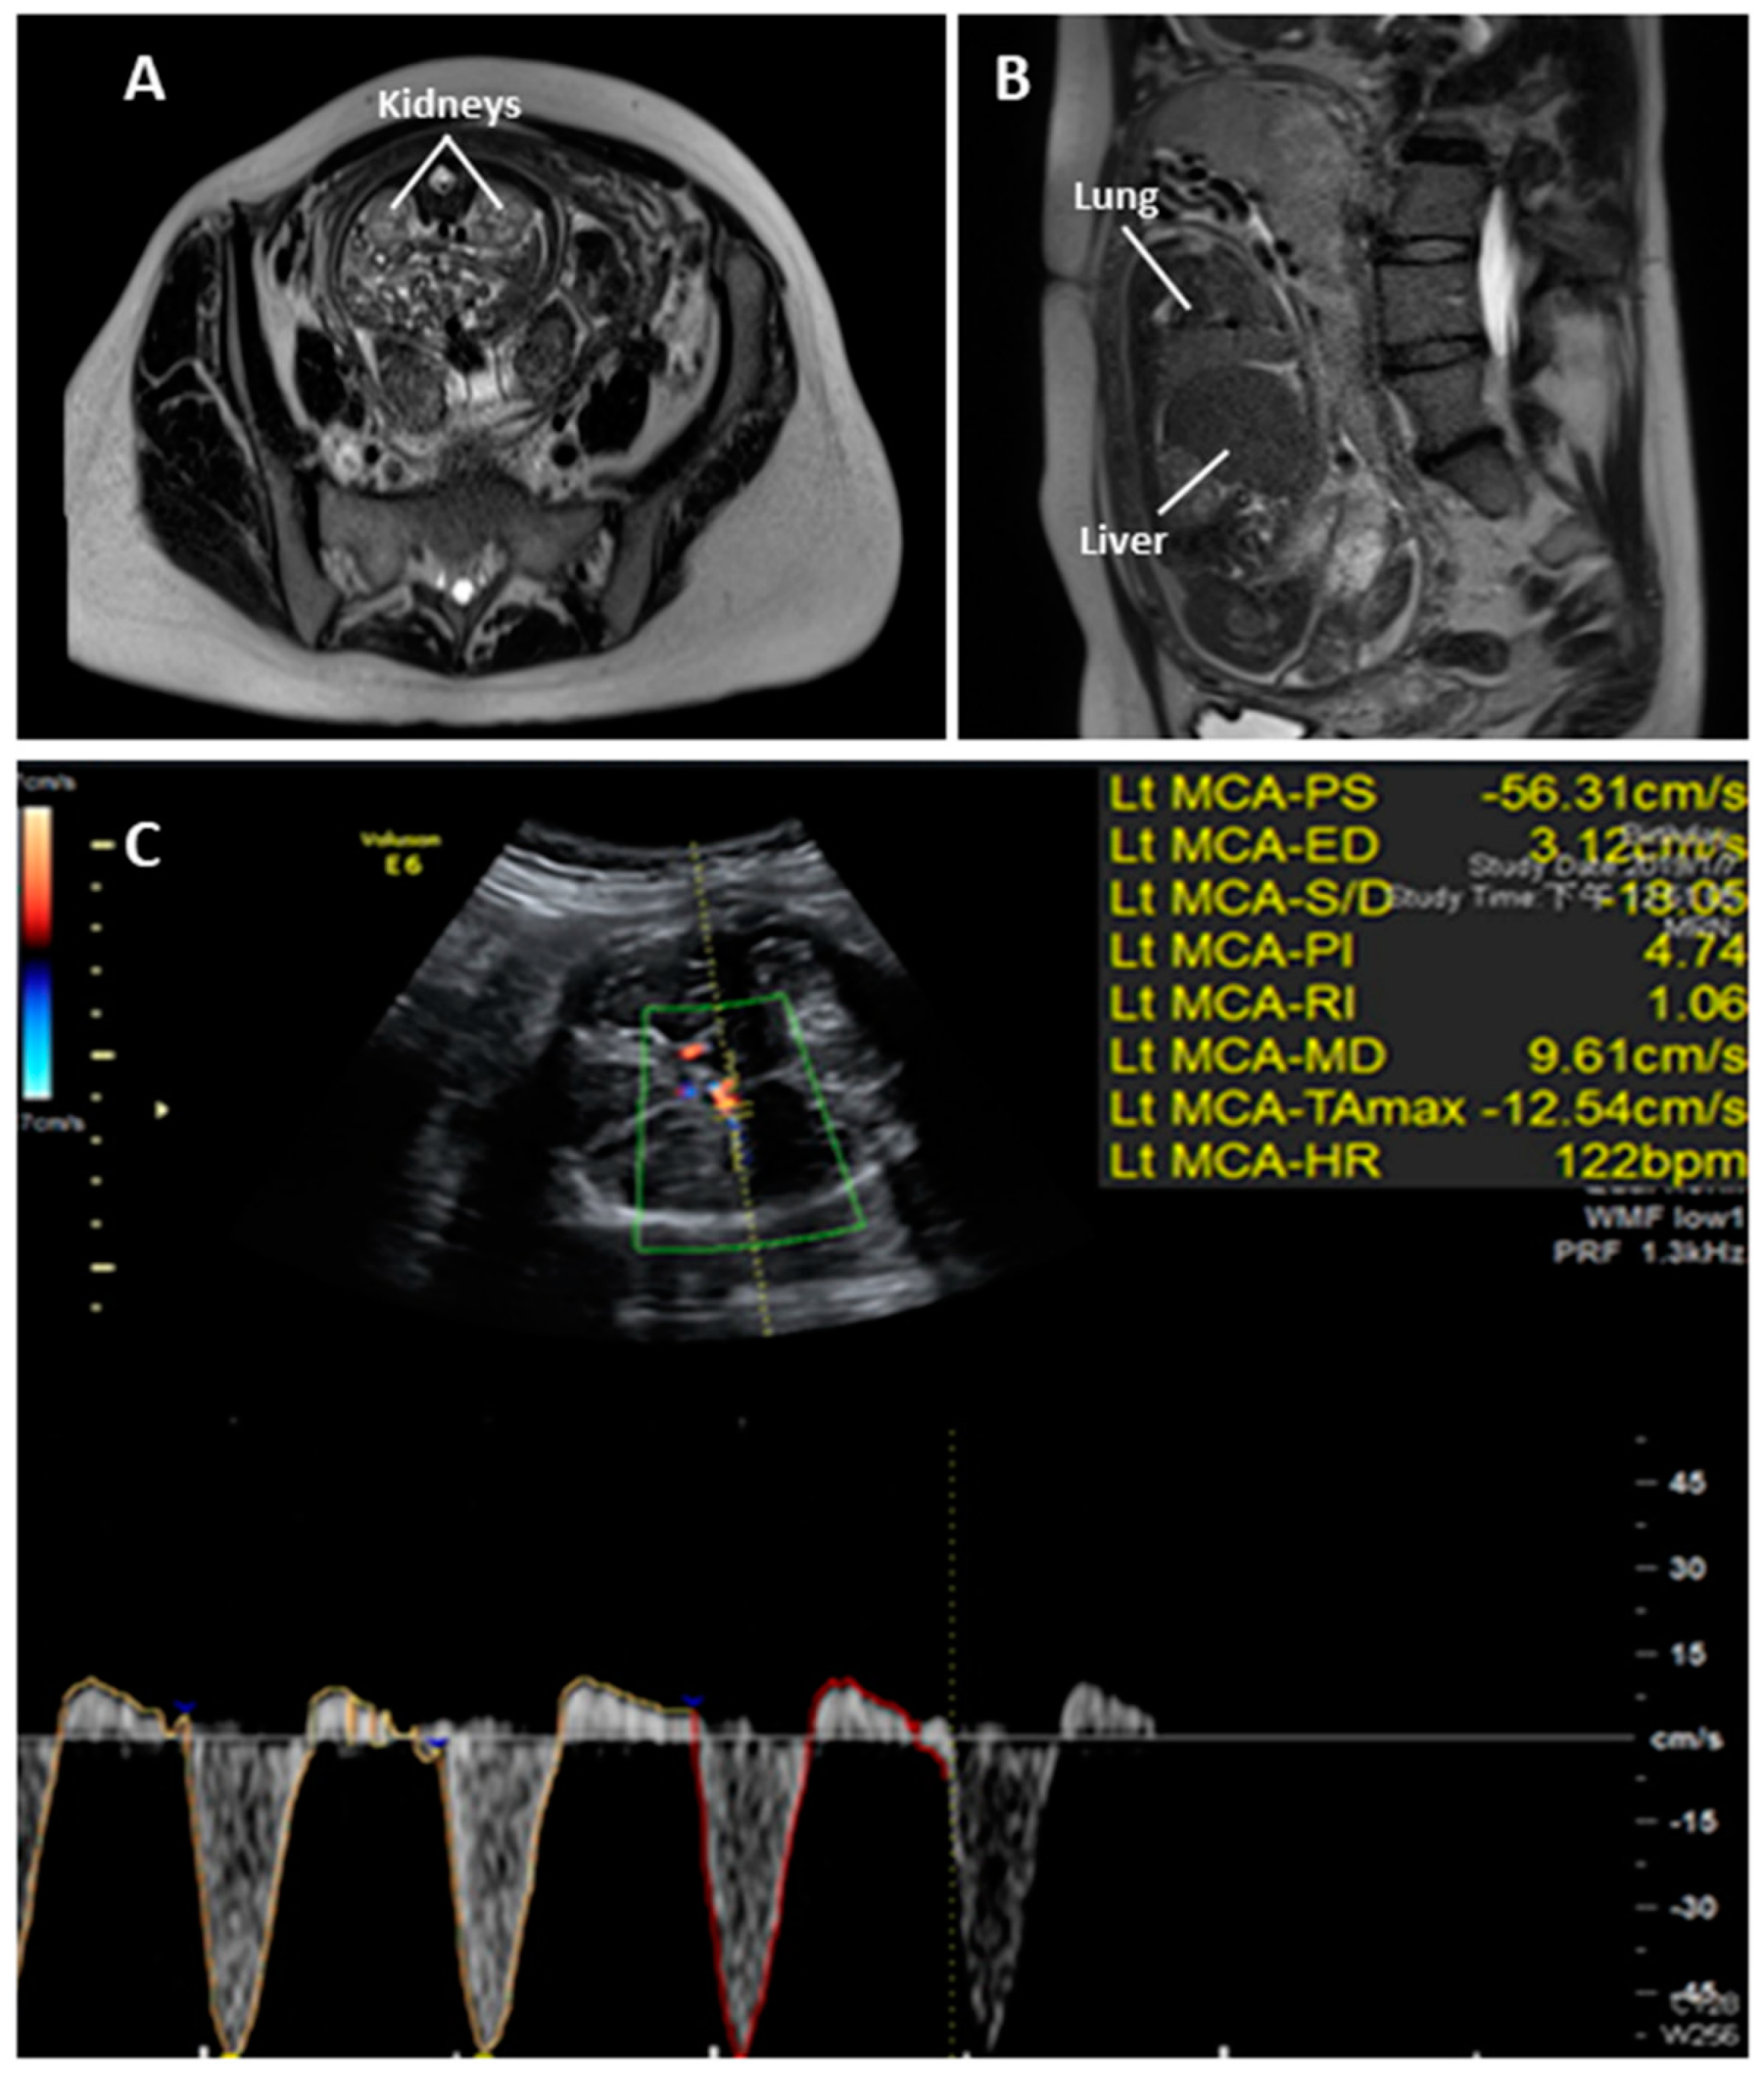

2. Case Report